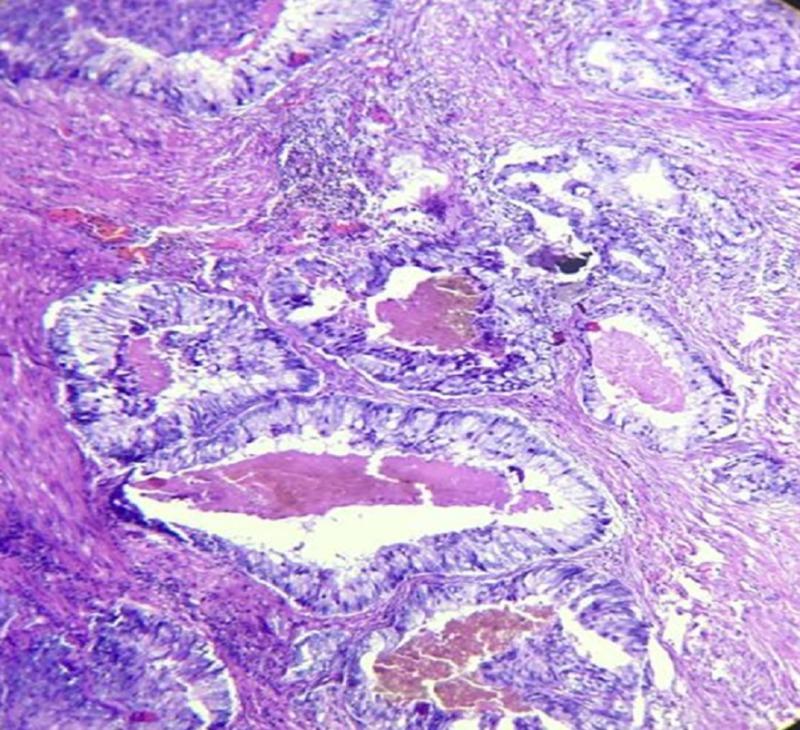

Prostatic ductal adenocarcinoma, is an uncommon entity in the spectrum of prostatic carcinoma. Clinically it is different from common prostatic acinar adenocarcinoma. It is usually more aggressive than prostatic acinar adenocarcinoma. We are presenting a case report on prostatic ductal adenocarcinoma, a cystic variant of prostatic carcinoma in a 55-year-old man who complained of obstructive urinary symptoms with mildly raised prostate-specific antigen (PSA). On further evaluation in our radiology department a cystic lesion with enhancing polypoidal soft tissue component was noted in prostatic parenchyma. Histopathology confirmed the diagnosis of ductal adenocarcinoma.

前列腺导管腺癌是前列腺癌谱系中一种不常见的类型。在临床上,它与常见的前列腺腺泡腺癌不同。它通常比前列腺腺泡腺癌更具侵袭性。我们报告一例前列腺导管腺癌病例,这是一名55岁男性的前列腺癌囊性变异型,他主诉有梗阻性排尿症状,前列腺特异性抗原(PSA)轻度升高。在我们放射科进一步评估时,发现前列腺实质内有一个伴有强化息肉样软组织成分的囊性病变。组织病理学确诊为导管腺癌。